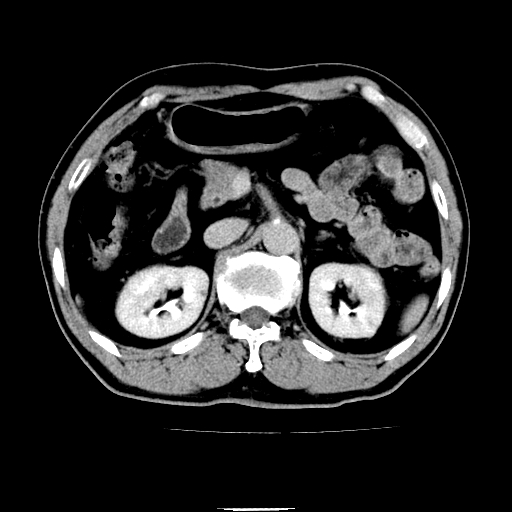

以下是引用chenqiong在2010-3-25 20:56:00的发言:[br]1、胆囊炎,胆囊息肉[br]2、肝内胆管及胆总管扩张,胆总管下端结石[br]3、十二指肠乳头旁憩室

以下是引用zxl51642在2010-3-26 10:47:00的发言:[br]胆囊炎,胆囊息肉,胆总管扩张,但未看到明显肿块,肝内胆管扩张不像恶性,炎性狭窄或阴性结石可能吧,建议mrcp,右肾小囊肿